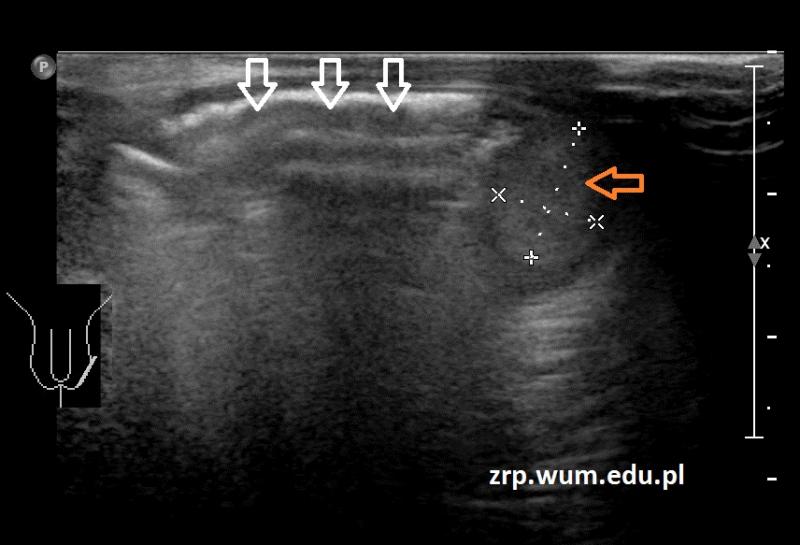

Przypadek 50: 2-miesięczny chłopiec zgłosił się na badanie usg z podejrzeniem przepukliny pachwinowej lewostronnej.

Rozpoznanie: W badaniu usg - uwidoczniono przepuklinę pachwinowę lewostronną - w kanale pachwinowym i w mosznie po stronie lewej widoczne pętle jelitowe (białe strzałki), z zachowaną perystaltyką. Oba jądra widoczne w mosznie, o prawidłowej strukturze i wielkości (czerwona strzałka - jądro prawe, pomarańczowa strzałka - jądro lewe, widoczne poniżej pętli jelitowych).